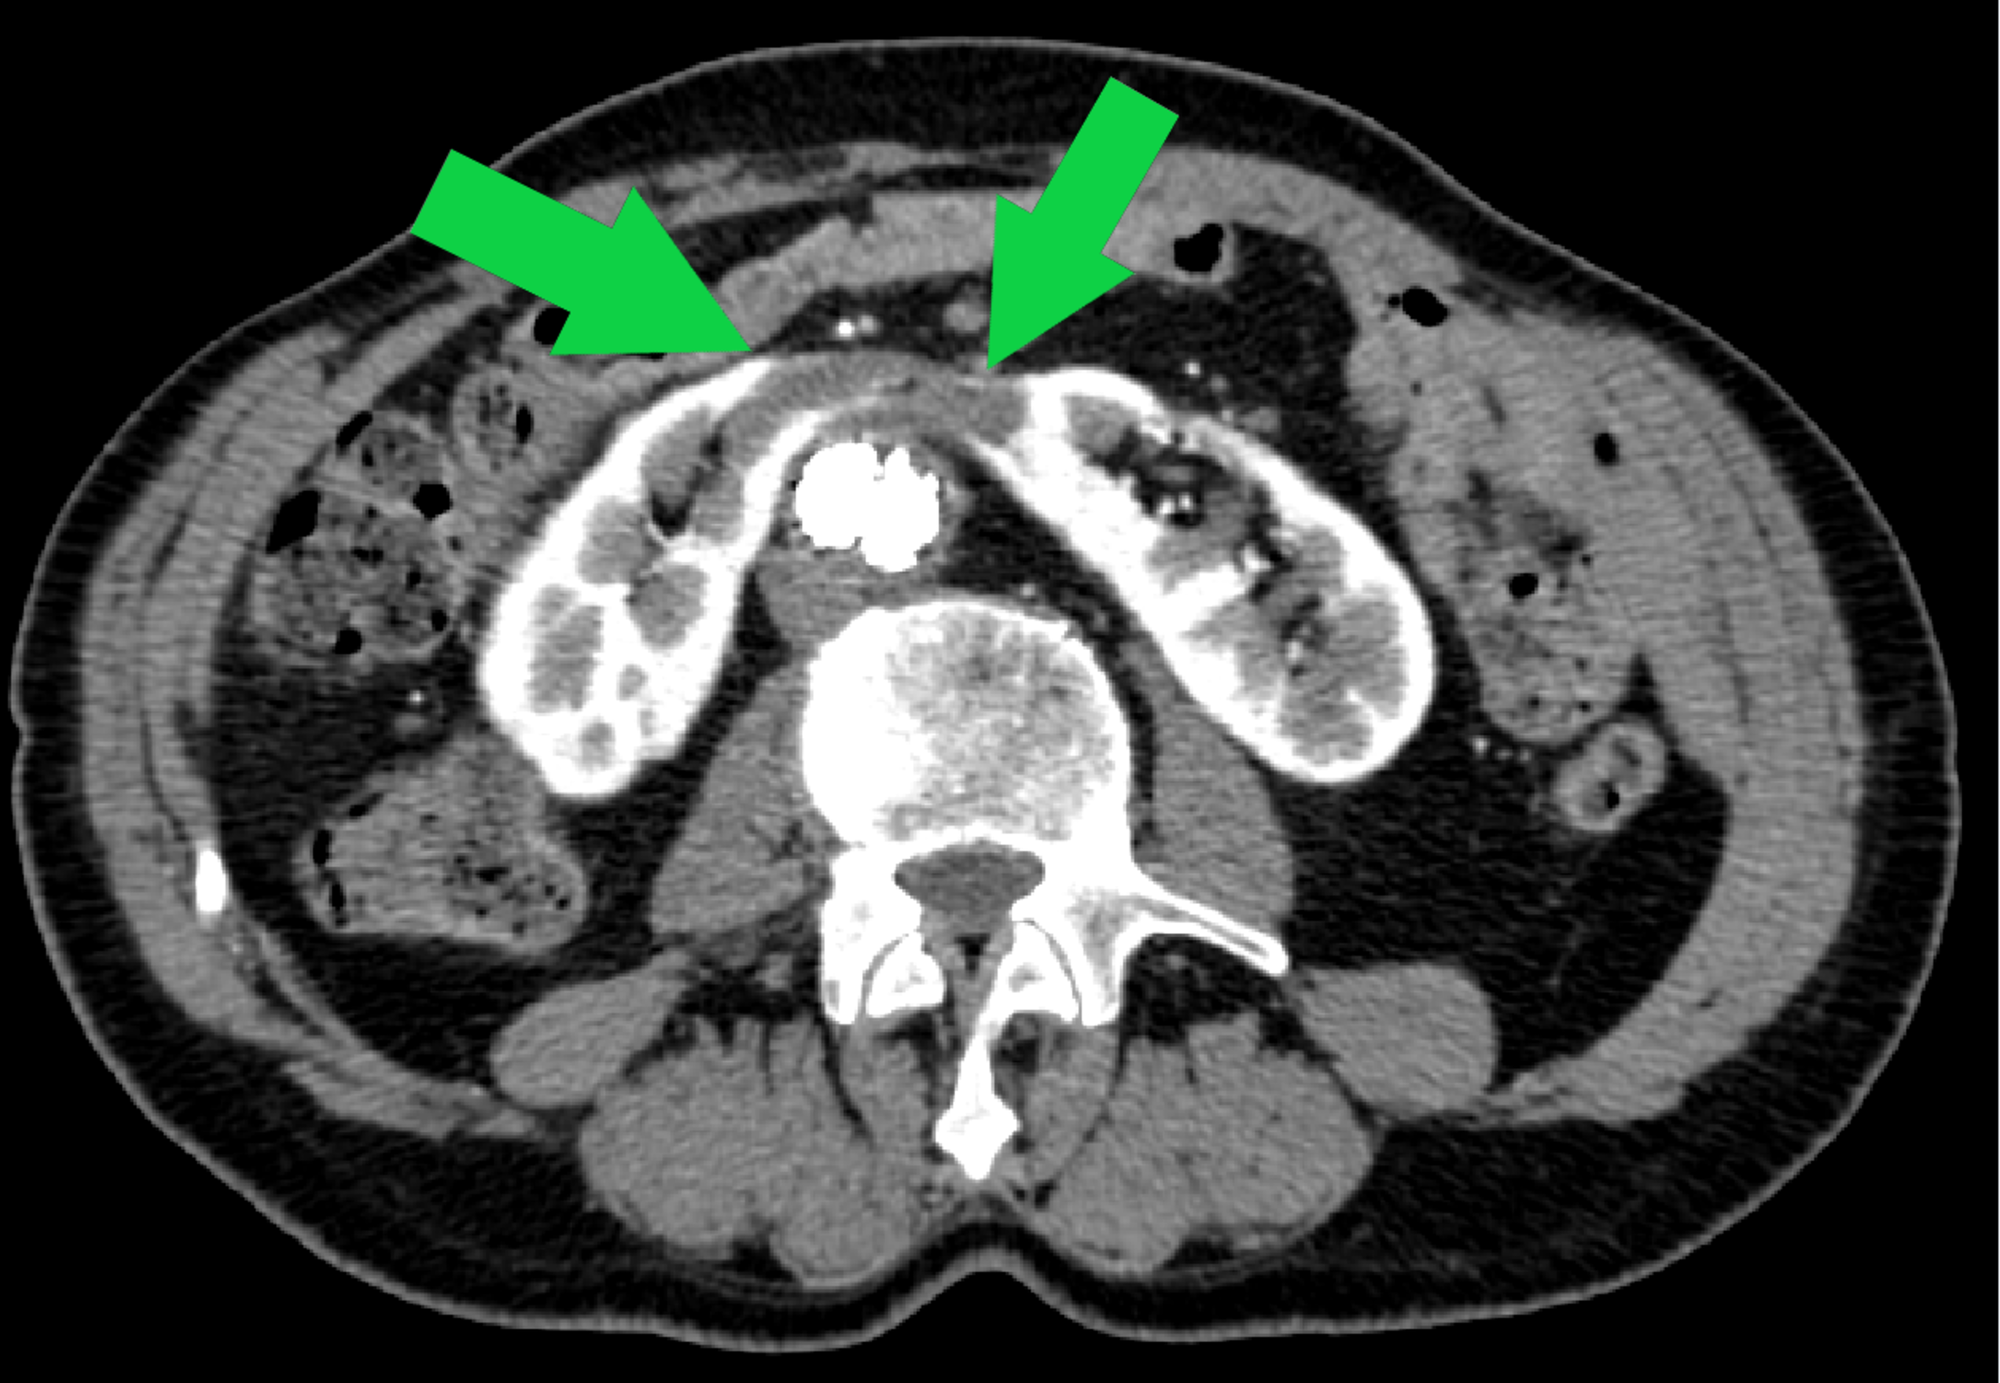

From www.researchgate.net

Transverse sectional view of the right horseshoe kidney on CT scan Horseshoe Kidney Surgery Management of renal cancers in horseshoe kidney patients is essentially the same as in normal patients. Horseshoe kidney, or renal fusion, occurs when two individual kidneys fuse together as they rise from the lower belly. Get the facts on causes,. In 9 out of 10 cases, the kidneys fuse at the bottom, forming a. Traditionally, the surgical approach has been. Horseshoe Kidney Surgery.